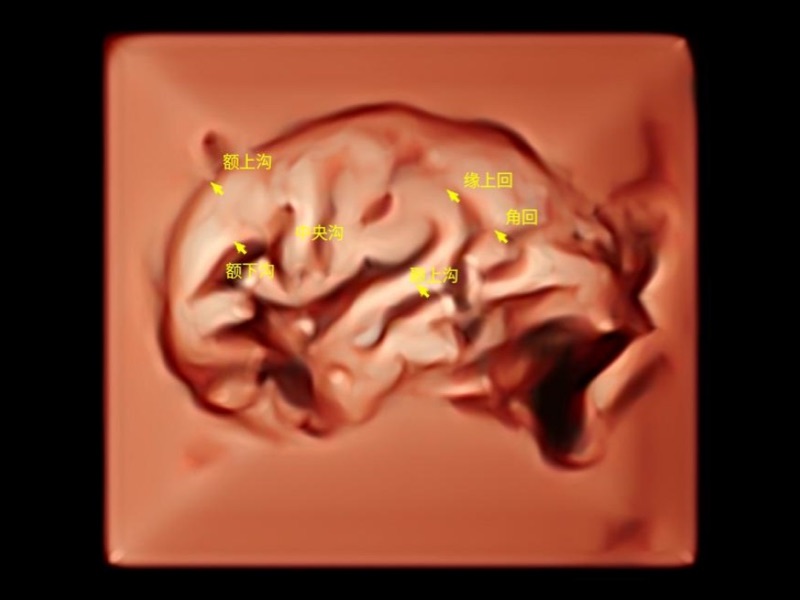

作為開立醫(yī)療全新打造的超高端旗艦超聲產(chǎn)品,從探頭抬起喚醒開啟掃查到多維探頭發(fā)射接收,通過先進(jìn)的場(chǎng)成像發(fā)射、自適應(yīng)聚合重建等技術(shù),基于RF Data原始射頻數(shù)據(jù)在圖像生成、高端功能等方面實(shí)現(xiàn)突破,為婦產(chǎn)科、兒科提供全方位臨床解決方案。

天工開物 智見蒼穹

獨(dú)有場(chǎng)成像發(fā)射技術(shù)

自適應(yīng)聚合重建技術(shù)

獨(dú)家XPUs混合硬件架構(gòu)

構(gòu)建多維智能生態(tài)